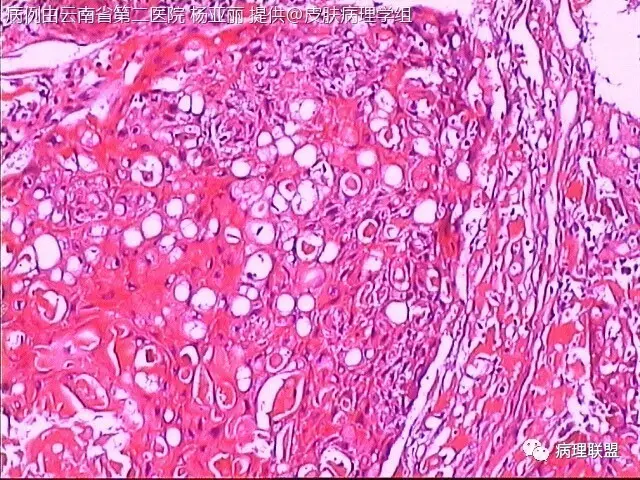

M/53 左手食指包块(皮肤鳞癌VS转移性鳞癌)

请各位老师帮忙看看,男性,53岁,左手食指包块 (病例由云南省第二医院 杨亚丽 提供,致谢!)

鳞癌没有问题。问题是否是转移癌:有否与表皮相连,病史演变如何?

@邓永键 谢谢邓主任,据说病人鼻子上有肿瘤才来切的手上的小包块,右手有,左手也有三四个,等我再问问鼻子上的是什么。看着细胞异型不明显,生长方式倒是确实不好。第6图有和表皮的关系,不相连,邓老师,鼻子上的肿瘤确实是鳞癌,这么说来手上的是转移的就很合理了。邓主任真是高,佩服!